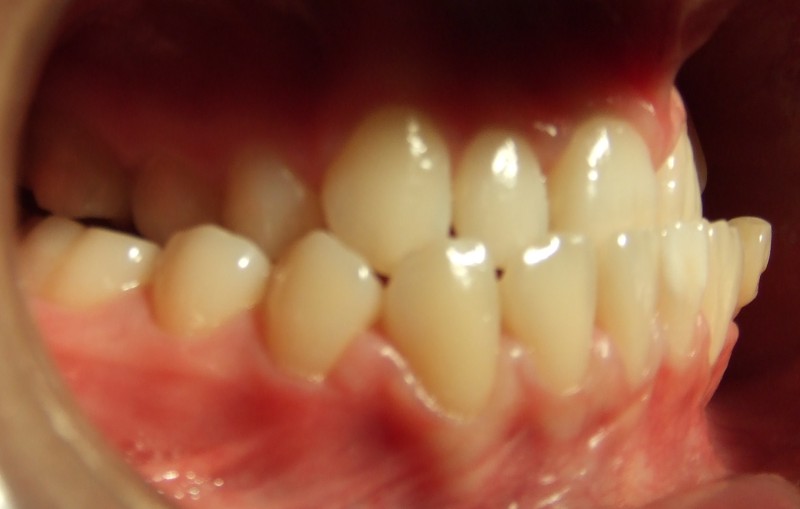

Malocclusion: Check for these symptoms

The most spot on symptom is tooth being crooked or moving out. Some people suffer from overbite which means that the upper teeth are sticking out. On the other hand certain people suffer from under bite which means the lower front teeth sticks out more than the upper ones.